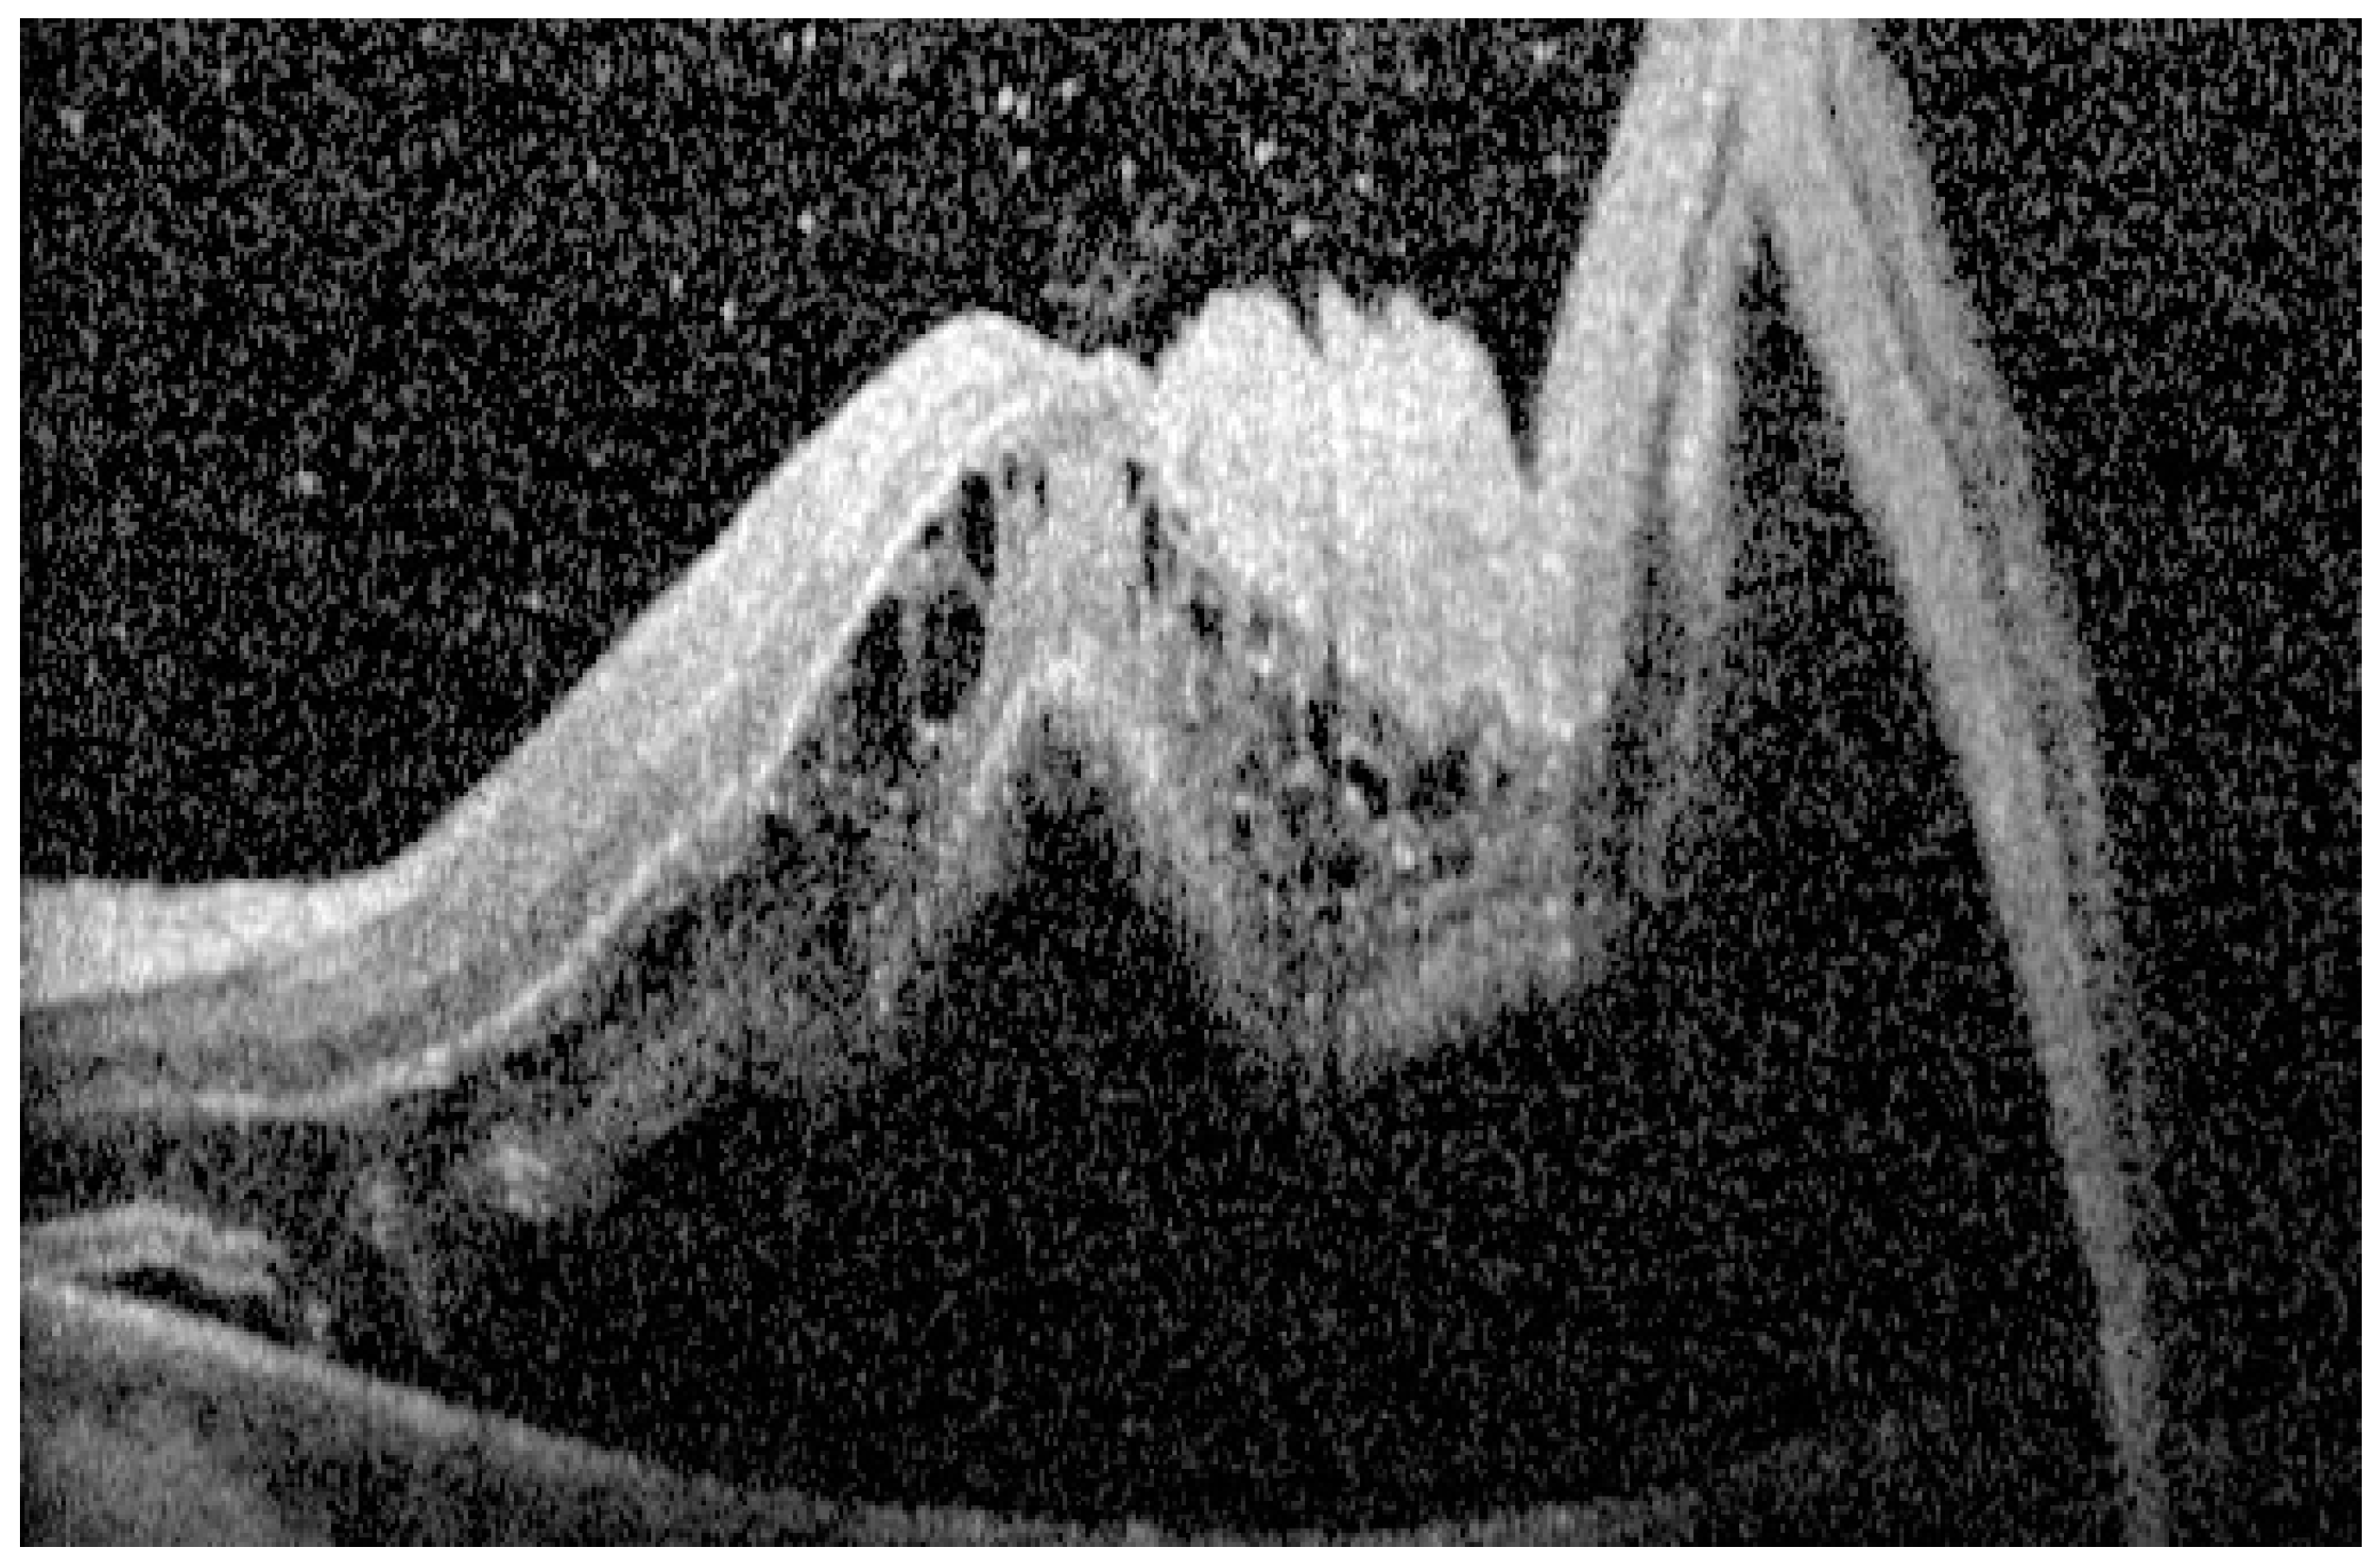

| Intraretinal cystic cavities (ICCs) | Well-delineated, hyporeflective spaces found within retinal layers secondary to fluid accumulation | Limited ICCs may have little impact, whereas extensive involvement predicts poorer visual acuity [14,16,23,32,37,38,39,40] |

| Outer retinal corrugations (ORCs) | High-frequency undulations in outer retinal layers | The presence of ORCs has been associated with poorer visual prognosis, and may indicate a more severe retinal disruption [42,43,44,45] |

| Outer retinal undulations (ORUs) | Directional changes in the outer retinal contour | More common in subacute detachments, may serve as a marker for detachment duration and potential for reversible damage [17,33] |